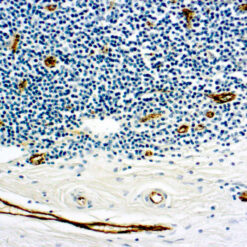

This antibody recognizes insoluble elastin, α-elastin, soluble non-cross linked precursor of elastin (tropoelastin). Elastin is an important polymeric protein of connective tissue that imparts elasticity to vertebrate elastic tissues.

| Clone | BA-4 |

| Immunogen | Bovine α-elastin |

| Positive Control Tissue | Heart, Kidney |